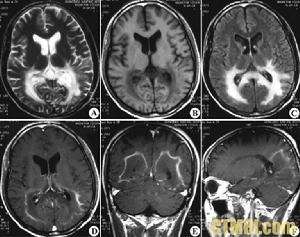

腎上腺腦白質退化症CT片腎上腺腦白質退化症英文名稱為Adrenoleukodystrophy,簡稱ALD,是一種X性聯隱性遺傳性的神經退化疾病,其缺陷基因位於X染色體上。

ALD致病機轉為X染色體上的ABCD1基因缺乏,這種異常基因會使細胞內過氧化物體peroxisome超長鏈飽和性脂肪酸(very long-chain fatty acids, VLCFA)代謝異常,使體內的超長鏈脂肪酸異常沉積在大腦白質和腎上腺皮質,侵蝕腦神經系統的髓鞘質,進而妨礙神經的傳導。 ALD發生率約為一萬六千八百分之一至二萬一千分之一,發病年紀不一,症狀包括過渡活躍、語言理解能力下降、記憶力下降、手腳控制不良,至肌肉痙攣、吞咽困難等,以最典型的兒童大腦型而言,會先喪失行動自主能力、語言能力,平均發病年齡為7歲。台大醫院基因醫學部主治醫師胡務亮表示,腎上腺白質退化症(ALD)多發生在四至八歲的男孩身上,病程平均約歷時兩年。